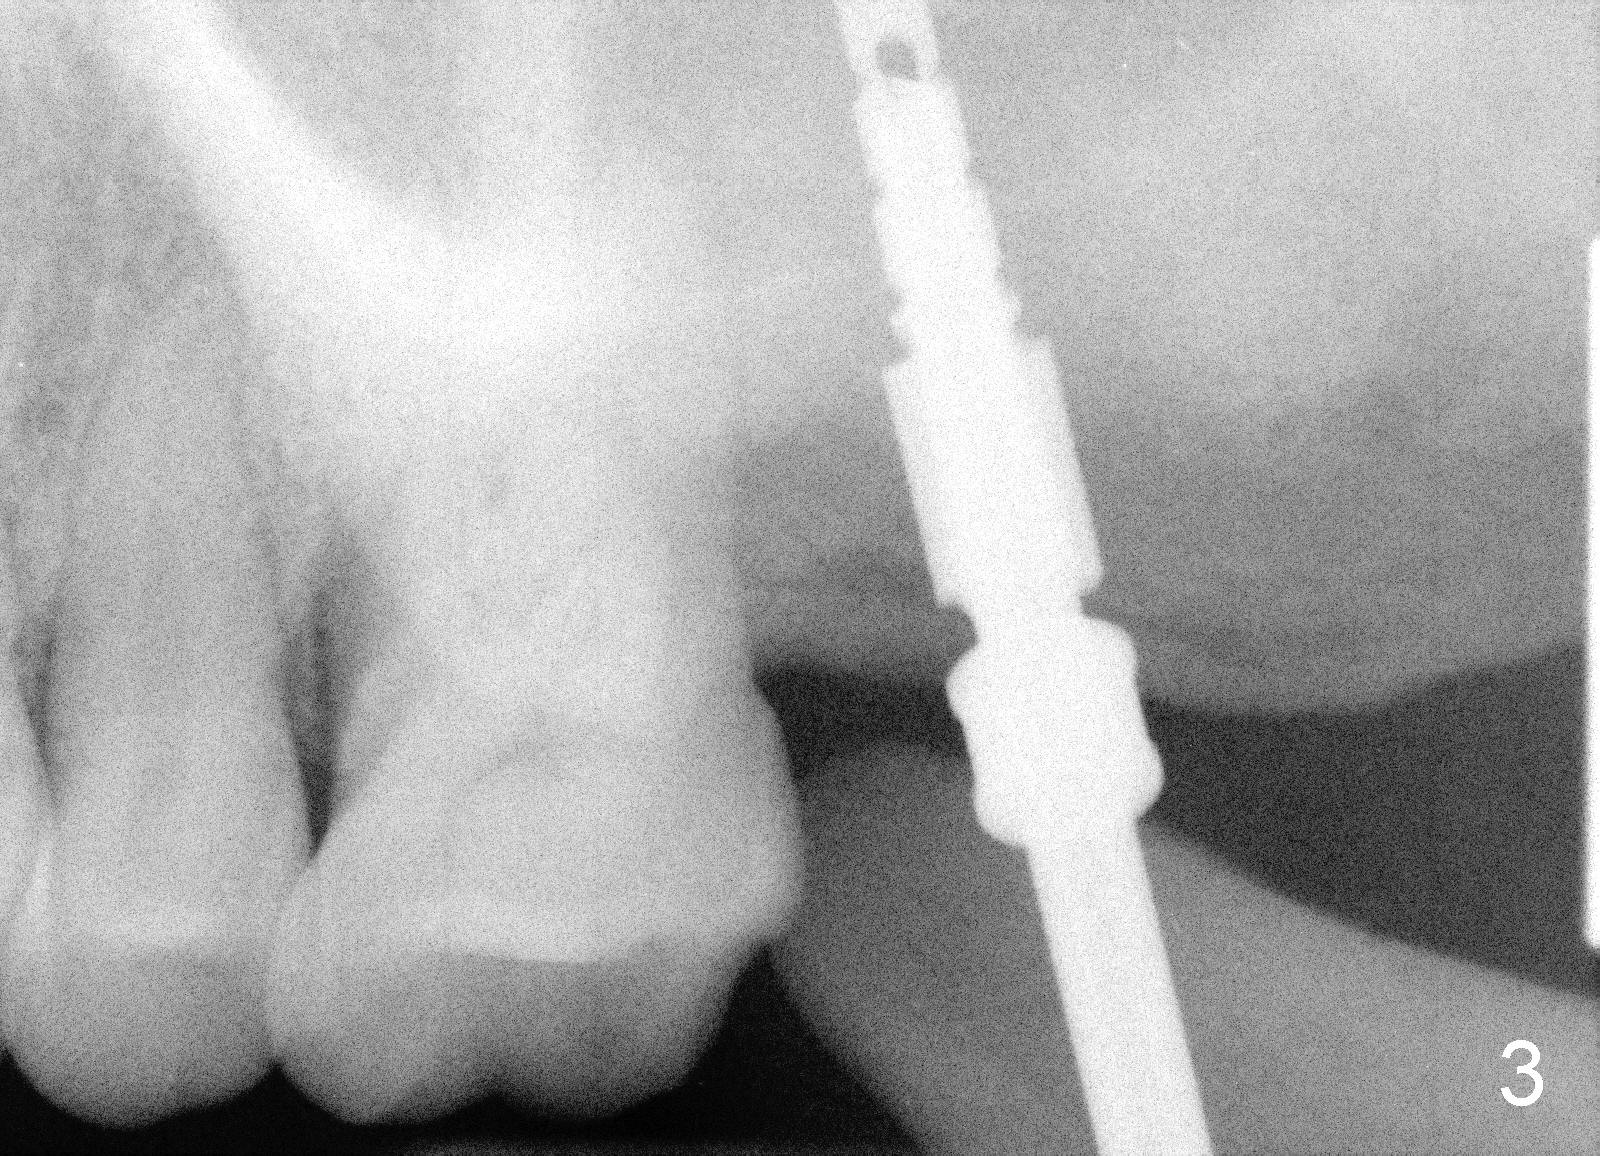

A 50-year-old lady presented to clinic with chief complaint of a loose tooth upper left.  The tooth #15 has complex endo-perio disease (Fig.1,2).  It was extracted on November 29, 2012.  She returned to clinic for implant placement on January 28, 2013.  Under local anesthesia, osteotomy was prepared with combination of bone expansion and drilling (Fig.3: 4x14 tapered drill).  She was not comfortable with tapping.  Finally, Tatum tapered implant (6x14) was placed (Fig.4) with 35 Ncm.  She felt dizzy when she stood up from dental chair. She felt better by the evening of January 29, 2013.  But the following morning, she did not feel good.  She wonders when the symptom will disappears.